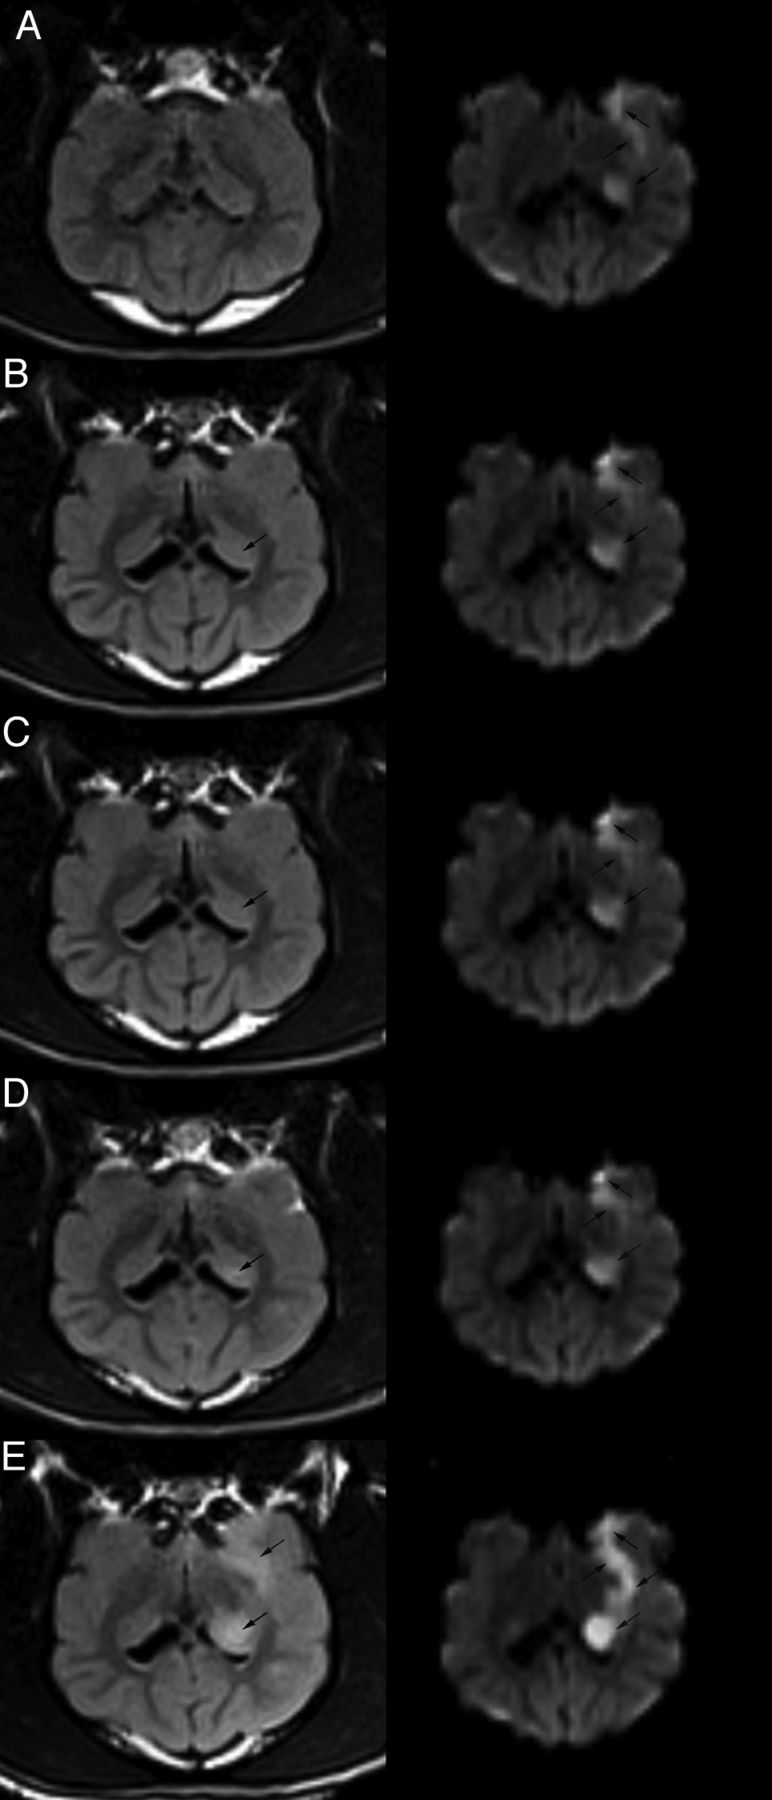

All 20 cerebral ischemic models were established successfully without any procedure-related complications or casualties (Fig 1). DWI+ lesions were seen in all 20 beagle dogs starting from 3 hours after embolization. The DWI indicated that the cerebral ischemic lesions were located on the ipsilateral caudate nucleus and the cortical area of the temporal lobe. Generally, the ischemic lesions were first found at the caudate nucleus, followed by the lesions located in the cortical area of the temporal lobe (Fig 2).

Sequential DWI and FLAIR images of coronal sections. The DWI and FLAIR were performed at 3 hours (A), 4 hours (B), 5 hours (C), 6 hours (D), and 24 hours (E) after embolization, respectively. There was no signal abnormality at 3 hours on the FLAIR image (A, left). Relative slightly high signal intensity area (arrow) with ovoid shape was observed in the left caudate nucleus on 4-hour FLAIR image (B, left). Increased high signal intensity was seen at 5 hours, 6 hours, and 24 hours on the FLAIR image (C–E; left), and lesions in the cortical area were seen on the 24-hour FLAIR image (E, left). Sequential DWI of coronal sections was all positive from 3 hours to 24 hours after model establishment (A–E; right).